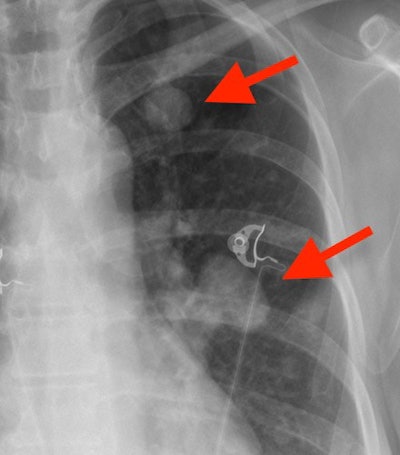

- Nodule: A lung nodule is often rounded and well-defined, representing an island of tissue surrounded by the air of the lungs. Visualized as rounded densities on chest x-ray, nodules can represent benign and malignant conditions, including lung cancer. If a nodule is suspected on a chest x-ray, CT is often necessary to further evaluate it.

- Adenopathy: Adenopathy means abnormal lymph node enlargement. Normal-sized lymph nodes are always present in the mediastinum -- the center part of the chest between the lungs containing the heart -- but usually cannot be seen on a chest x-ray because they blend in with adjacent structures. Enlarged lymph nodes can sometimes be difficult to see, even for experienced radiologists. If a radiologist sees lumps and bumps around the heart and mediastinum that are not explained by normal structures, adenopathy may be present and a chest CT should be obtained.

- CABG: Doctors actually pronounce this abbreviation as "cabbage," but not to worry, you don't have sauerkraut in your chest. CABG stands for coronary artery bypass graft, often colloquially referred to by the number of bypassed heart vessels (e.g., triple bypass, quadruple bypass). Radiologists know you had a CABG on a chest x-ray because of the wires used to tie your sternum back together, called median sternotomy wires. Hopefully it is not a surprise to you or your doctor when the radiologist mentions your surgery on the x-ray report! The only problem a radiologist may notice is broken wires. If only a few wires break it is usually not a problem, but if most wires break soon after surgery the sternum can spread apart (called dehiscence) and fail to heal normally.